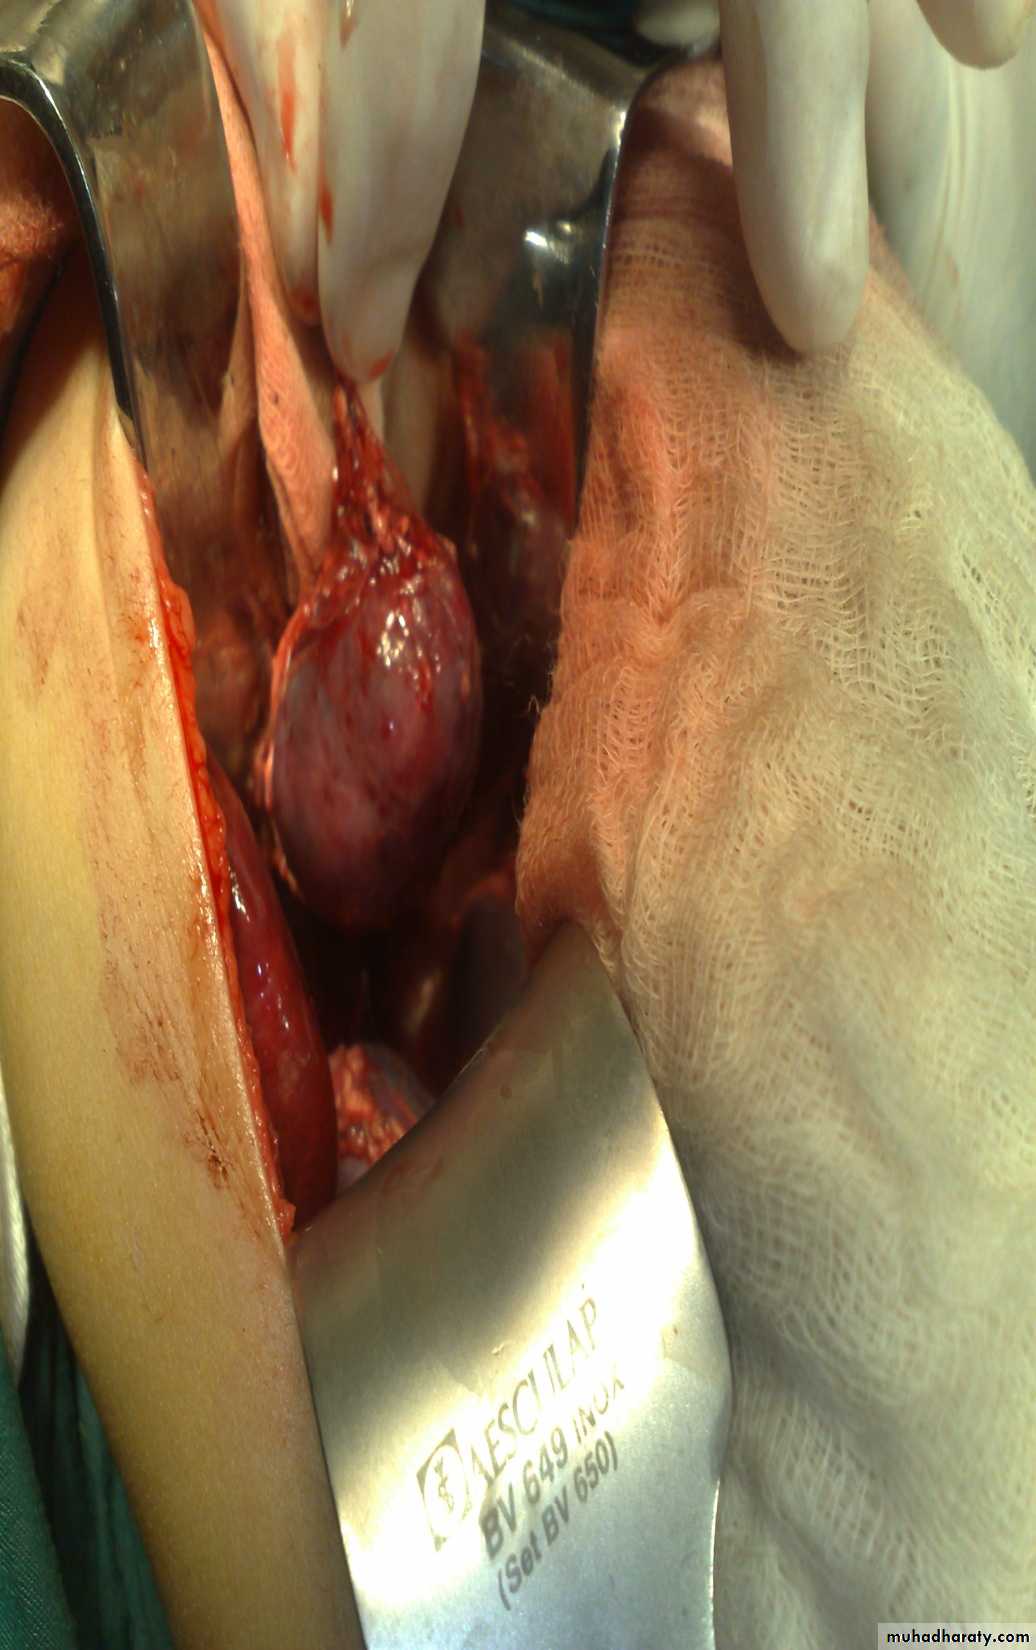

The Child with an Abdominal Mass

5 years child, presented with mass in the flank.

Dx: nephroblastomaDDx of mass in the flank:

Treatment by surgery remove the kidney + chemotherapy